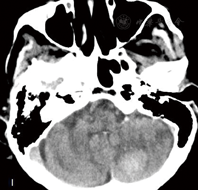

患者,女性,91岁,因"突发反应迟钝伴左侧上下肢无力1 d"入院。患者16 h前出现神智模糊,反应迟钝,活动减少,不愿进食,无呕吐,无二便失禁,无肢体抽搐;2 h前意识障碍加重,伴有头痛、呕吐,遂于安徽医科大学附属合肥医院急诊科就诊,急诊头颅CT提示左侧小脑出血(图1),收入神经内科。患者既往高血压病史多年,不规则服用降压药物,平时监测较少。查体:体温36.8 ℃,血压230/134 mmHg(1 mmHg=0.133 kPa),双肺呼吸音粗,未闻及干湿性啰音,心率100次/min,律齐,偶闻及期前收缩,未闻及杂音。神经系统检查:嗜睡状,问之无应答,额纹对称,双侧瞳孔直径2.5 mm,对光反射存在,双眼右向凝视,左侧上下肢肌张力低,肌力Ⅱ级,右侧上下肢肌力V-级,右侧上下肢肌张力正常,双侧巴氏征未引出。实验室检查:红细胞计数为3.99×1012/L,中性粒细胞计数为15.36×109/L,中性粒细胞百分数83.21%,白细胞计数为18.48×109/L,尿素氮25.50 mmol/L,肌酐382.0 mmol/L,血钾6.15 mmol/L。心电图提示窦性心动过速。头颅CT提示左侧小脑半球出血,双侧侧脑室旁、丘脑、脑桥大片状低密度灶。入院后即刻予以吸氧、心电监护、促醒、脑保护、抑酸护胃、补液支持、脱水降颅压、调节电解质紊乱等治疗,并静脉滴注硝酸甘油以0.25 mg/h调节血压。入院后约14 h患者出现高热达39.9 ℃、呼吸道分泌物明显,意识障碍进一步加重呈中-深度昏迷,考虑肺炎,予以抗炎、化痰、补液、促醒等处理,持续静脉使用硝酸甘油加量至1 mg/h,血压仍持续达(180~200)/(110~120)mmHg,降压治疗效果差,血尿素氮、肌酐进一步恶化。肺部CT提示慢性支气管炎、肺气肿、右肺炎;头颅MR提示双侧侧脑室旁、丘脑、双侧桥脑、中脑广泛T1WI低、等信号,T2WI及FLAIR像呈高信号,弥散加权成像呈低、等信号,表观扩散系数图无信号(图2、图3)。患者于入院后46 h神志转清,血压(120~130)/(80~90)mmHg,左侧肢体肌力恢复至Ⅳ级,要求下床小便,停用硝酸甘油,加用口服非洛地平缓释片5 mg,2次/d,联合厄贝沙坦氢氯噻嗪片1片,1次/d调节血压,余治疗继续予以原方案。半个月后复查头颅MR除小脑出血病灶存留,其余异常信号完全消失(图4)。入院25 d后患者病情稳定,血压120/70 mmHg,可自主进食、正常交流及下床自行活动,予以出院。随访1个月病情无反复。